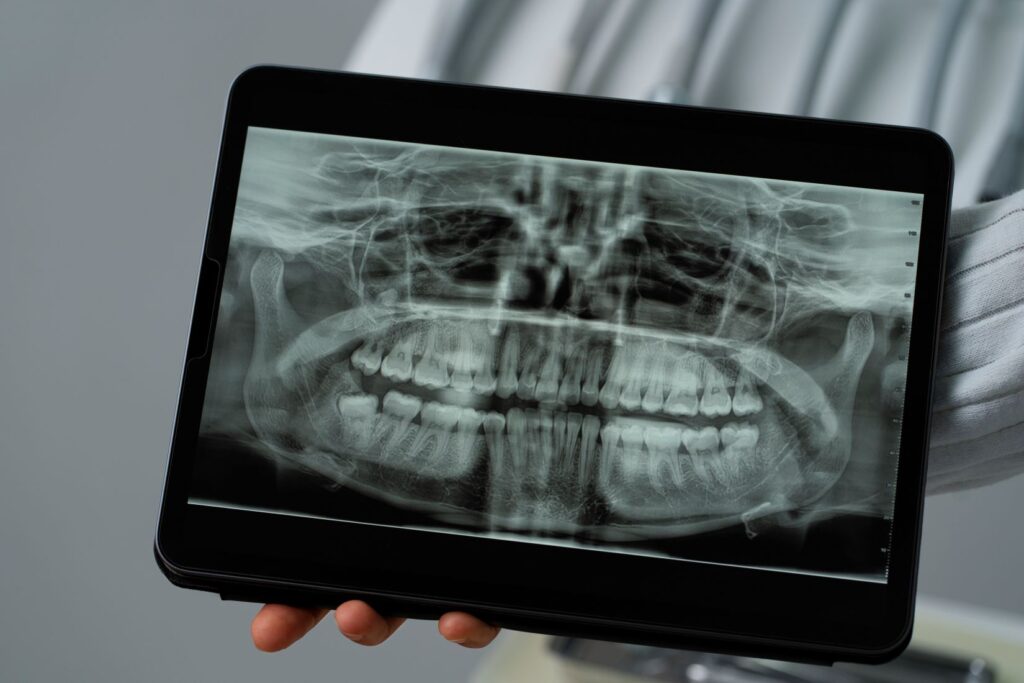

Gömülü Diş Nasıl Teşhis Edilir?

Gömülü dişlerin teşhisi klinik muayene ve görüntüleme yöntemleri ile yapılır.

Radyografik İnceleme

Gömülü dişin konumu ve çevre dokularla ilişkisi görüntüleme yöntemleri ile değerlendirilir.